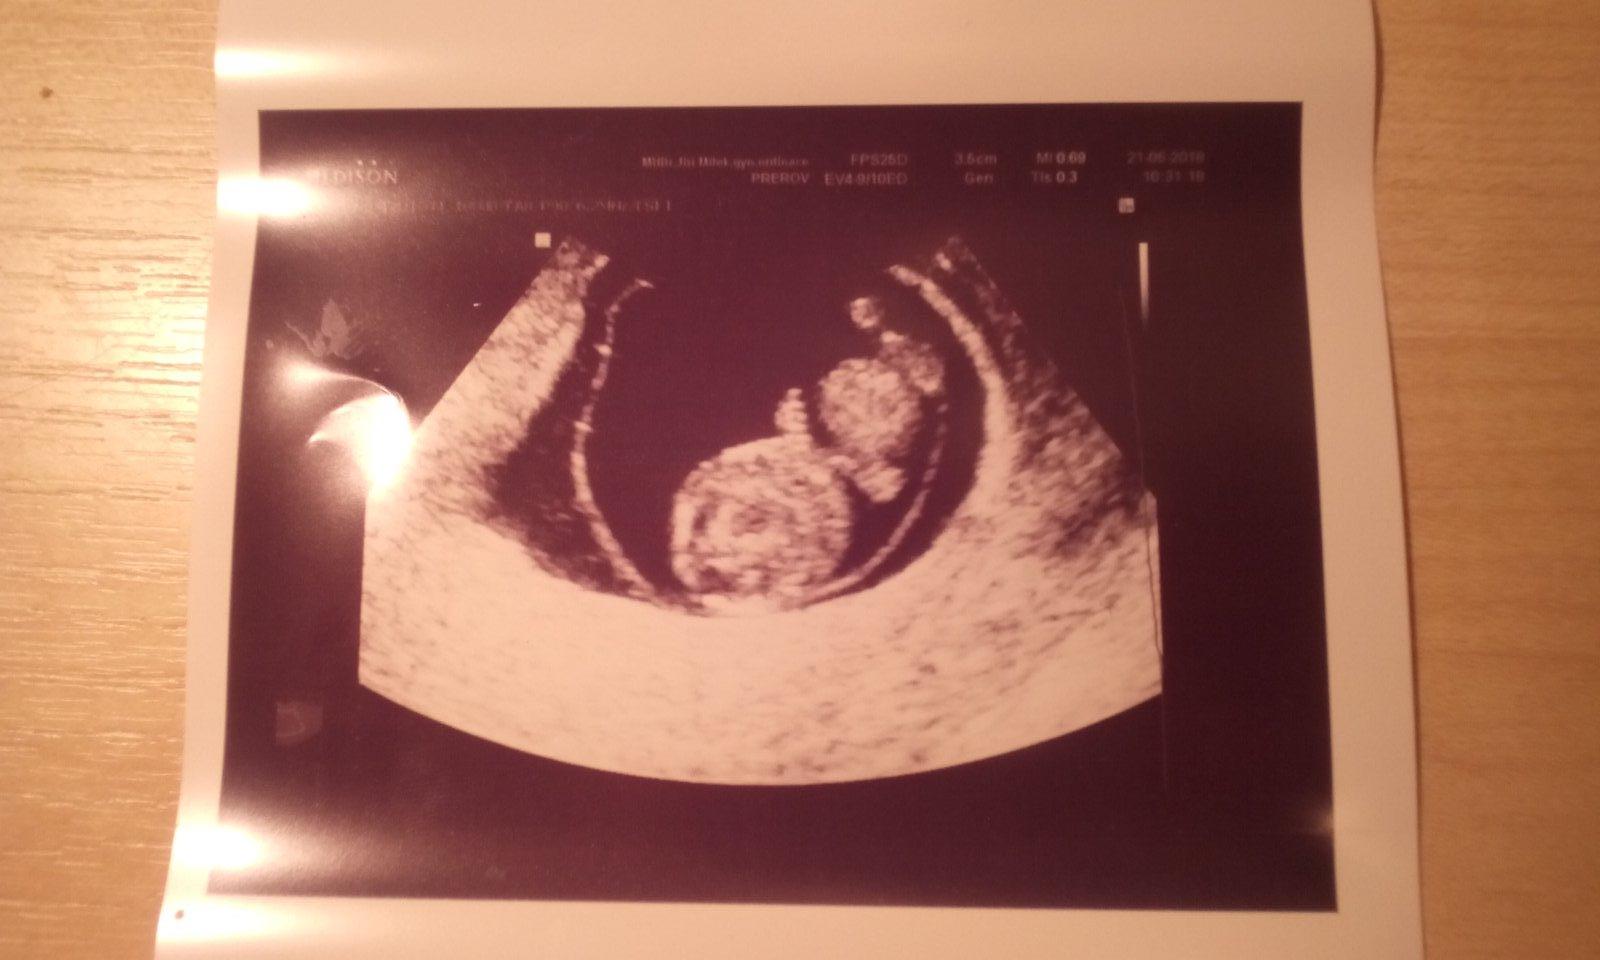

@krisatko To me moc mrzi. =( Určitě tentokrst vse dobře dopadne. Ja jdu tentokrat na screening az ve 13+4tt Tedy 12.7. kdyz sem se ptala, zda to není pozde, ze mi moje mudra rikala, ze to vyšetření mam mit hotove nejpozději do 5.7. tak sestra rikala, ze to počítají jinak, nez prakticky gynekolog a ze vyšetření se dela do 13+6tt. Tak snad doufam, ze to tak je. Celkem byla takova ustepacna po telefonu. 😹